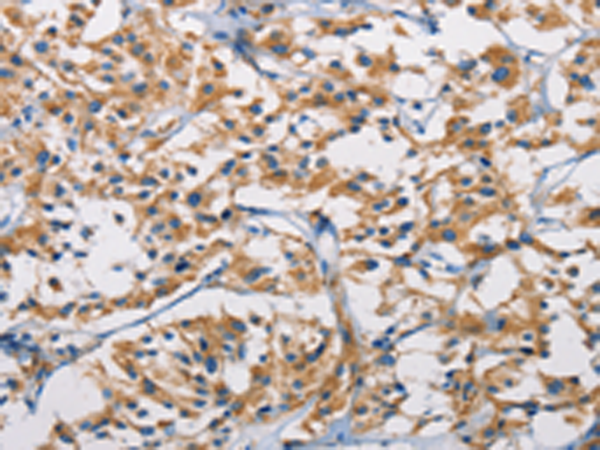

分类: 科研抗体货号: P07973别名: PIM应用: IHC反应种属: Human, Mouse, Rat

分类: 科研抗体货号: P08010别名: ZFYVE11; FYVE-DSP2应用: IHC反应种属: Human, Mouse

分类: 科研抗体货号: P07972别名: SHIK; SgK495应用: IHC反应种属: Human, Mouse, Rat

分类: 科研抗体货号: P08005别名: NT; eN; NT5; NTE; eNT; CD73; E5NT; CALJA应用: IHC反应种属: Human, Mouse, Rat